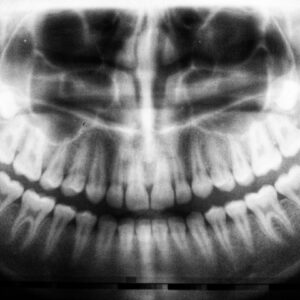

When you decide to explore dental implants, the first step is to understand the consultation process. This initial meeting is crucial as it sets the stage for your entire treatment…